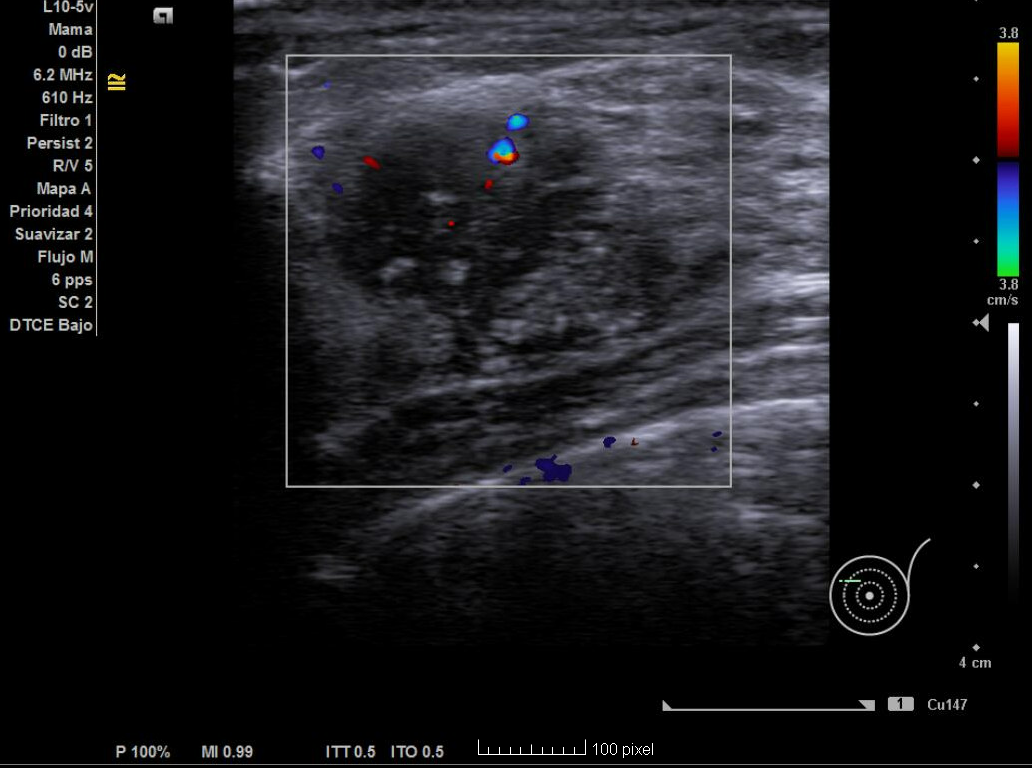

Ecografía no reglada en AP: nódulo de 2,3 cm x 1,4 cm con bordes irregulares no bien delimitados, hipoecoica, heterogénea en donde hay zonas espiculadas, con microcalcificaciones y captación Doppler en interior.